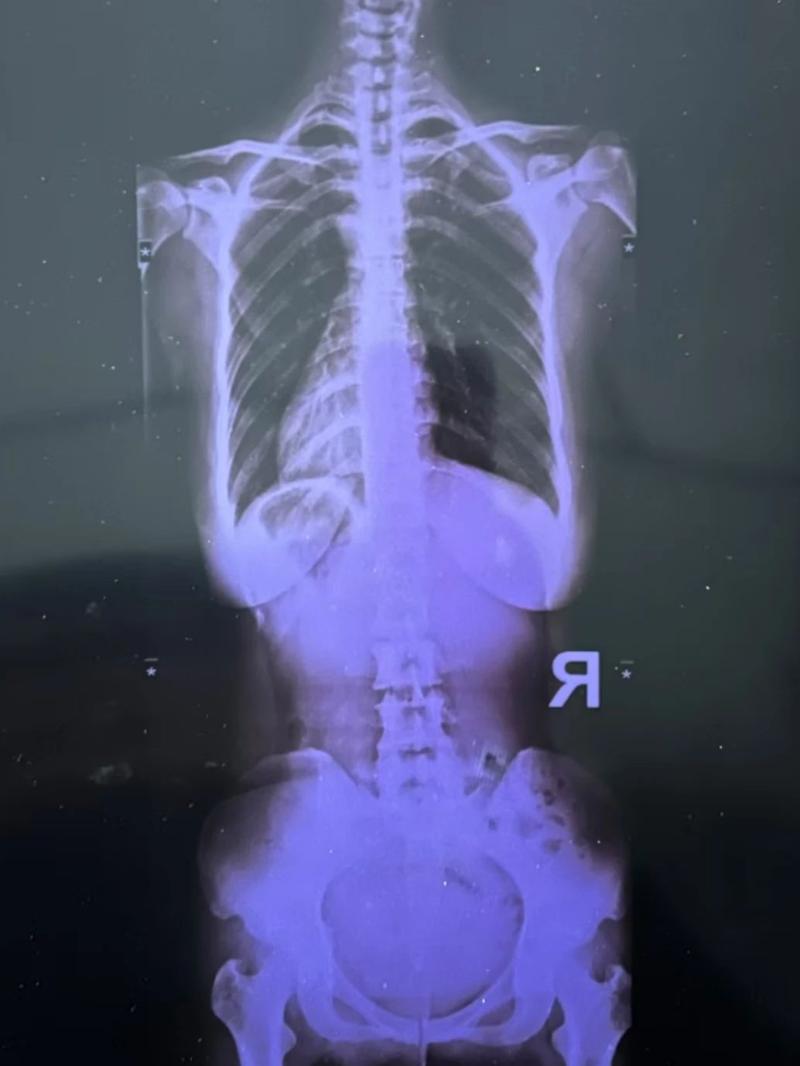

最近又疼起來嚴(yán)重影響正常生活,她前往醫(yī)院就診,結(jié)果查出了脊柱側(cè)彎11°,骨盆旋移,骶髂關(guān)節(jié)半脫位,由于這些導(dǎo)致頸肩,后背,腰部肌群代償出現(xiàn)問題,從而出現(xiàn)腰痛,后背痛,肩膀痛!